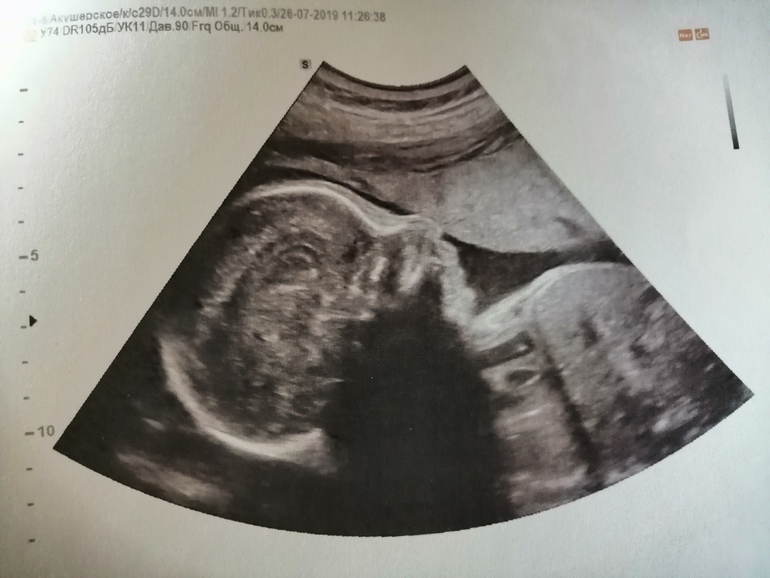

Гляньте, пожалуйста, на носик.

УЗИ, КТГ, доплерНе могу понять, он у малыша прижат так плацентой (или чем там) или такой и есть на самом деле? Как думаете? У дочки по-другому было, но они, как понимаю, у нас разные будут по внешности. Сынок на папу больше похож, мне кажется (в 3D смотрела). У него прямой, длинный, без горбинок и загибов.

Мне кажется это тонус надавил,тем более если у дочки другой и у вас с папой нет таких носов)

Да, это 26н2д, сегодняшнее)) ходила чисто для себя, фотки/видео на память сделать. Вот 3D.